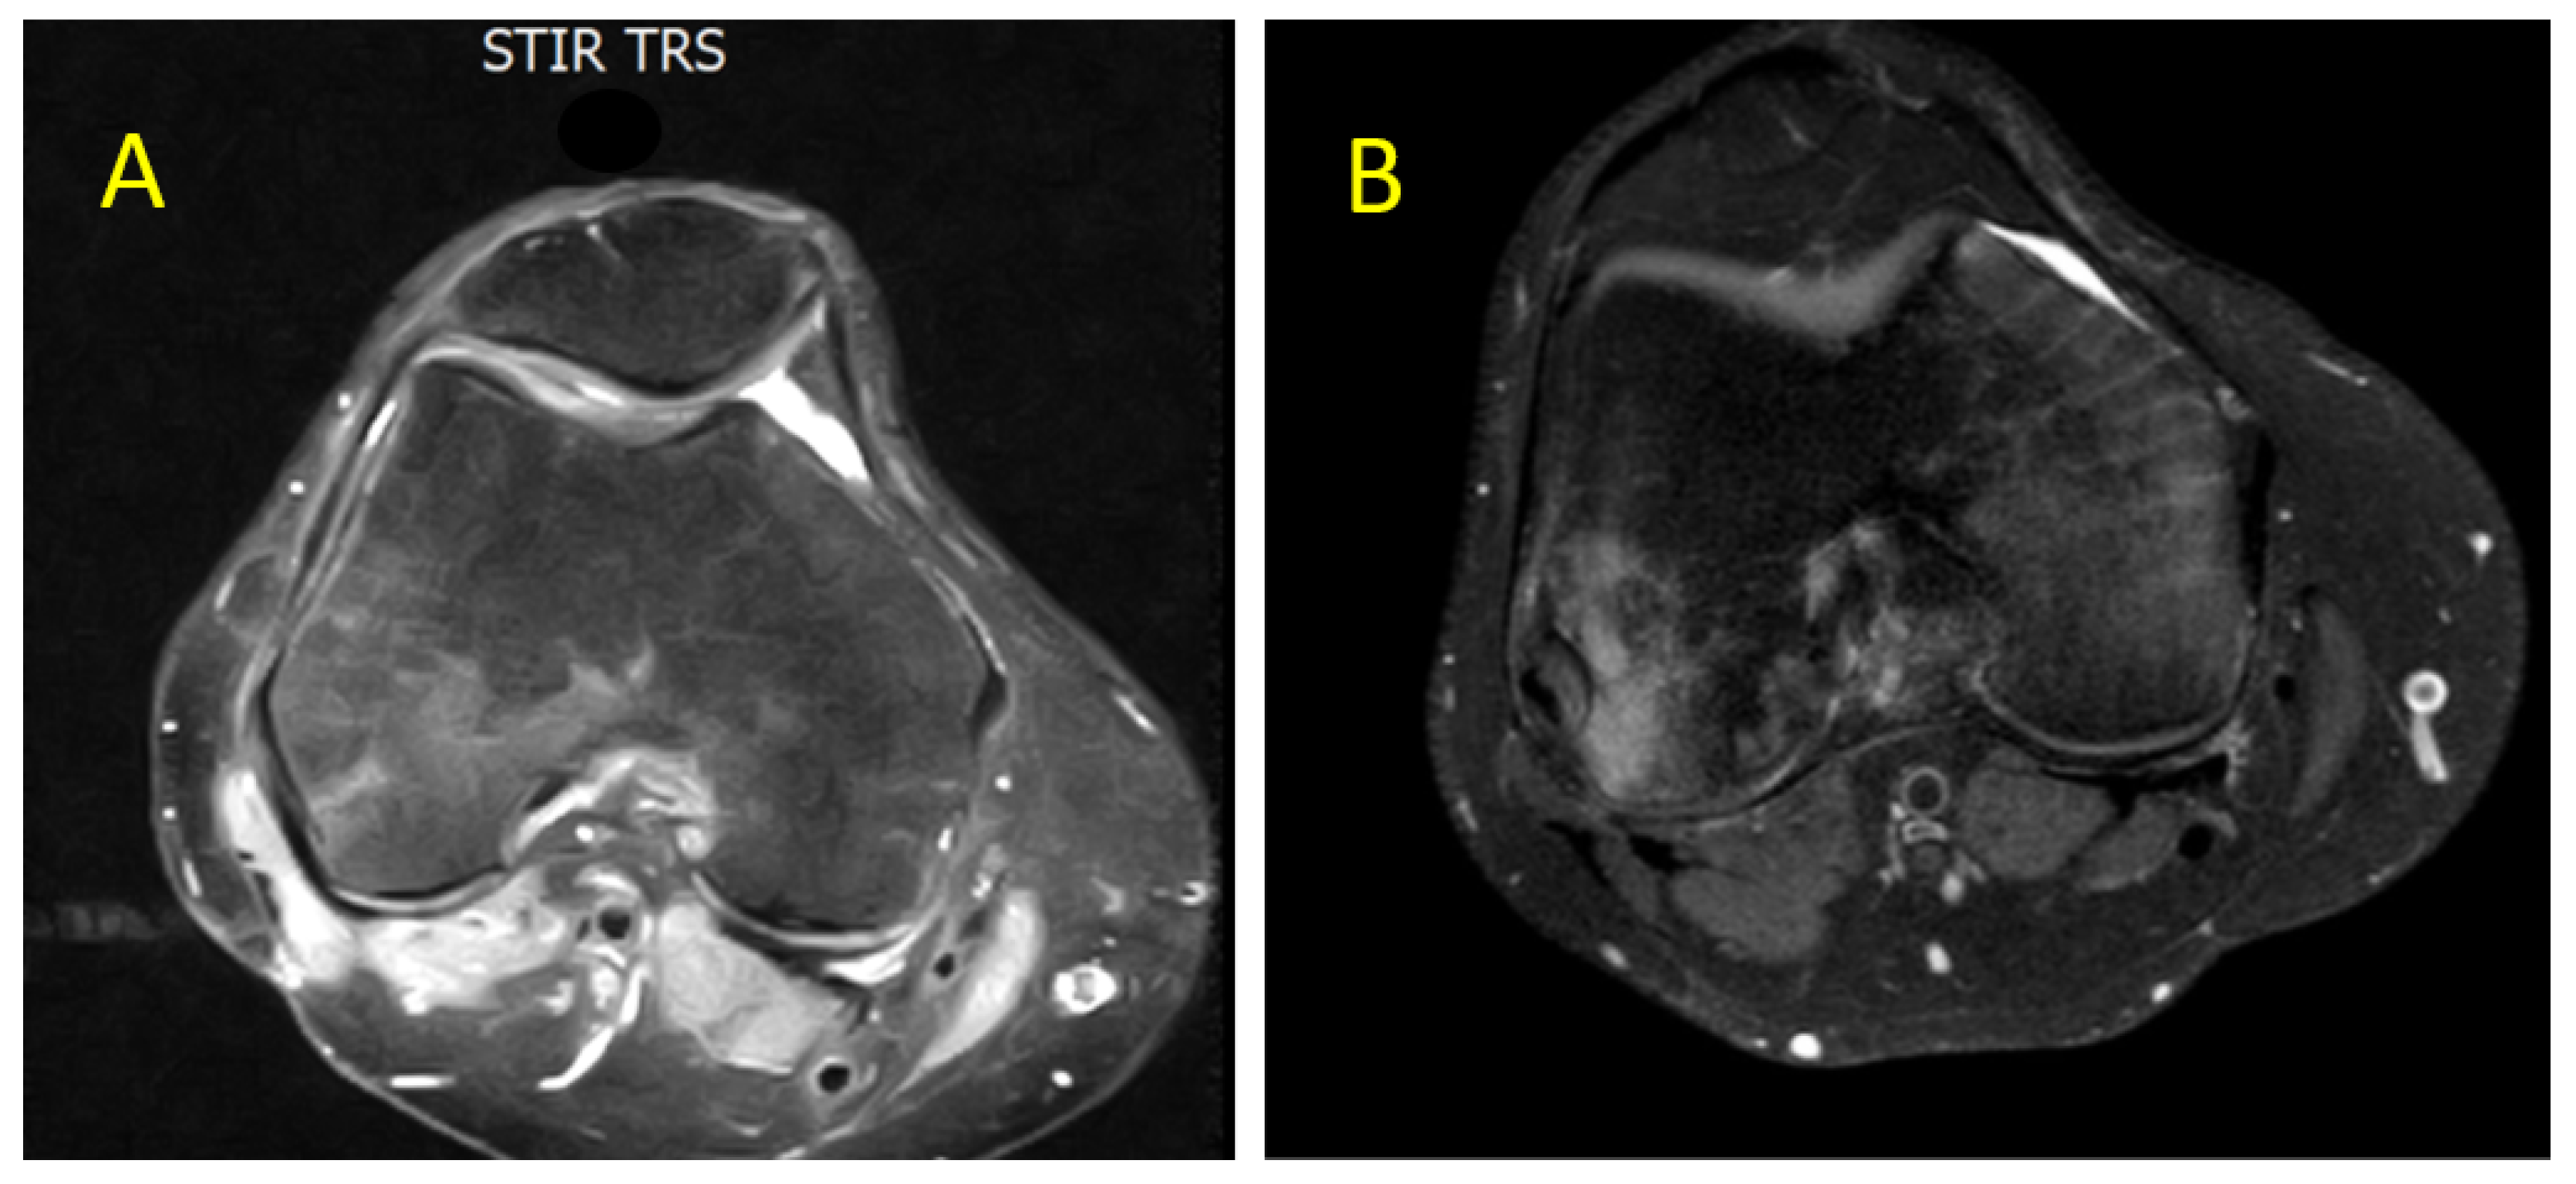

- CASE 1: A CML patient under dasatinib and imatinib treatment

- CASE 2: 60-year-old patient with imatinib therapy